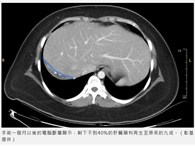

切除6公斤多囊腎 彰基活腎移植助教師重返講台

彰基醫學中心團隊以達文西手術切除兩側腎臟,由陳老師的妹妹捐贈活體腎臟完成移植。...